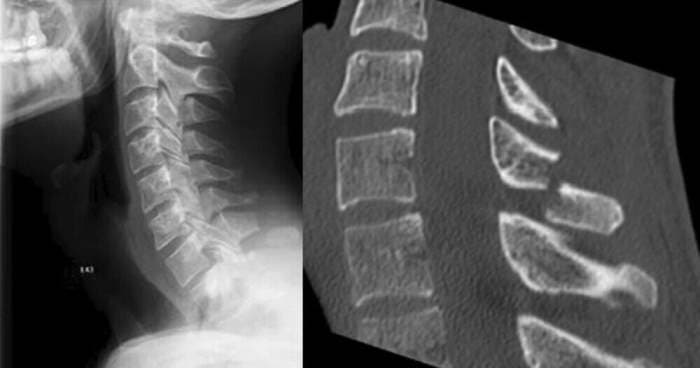

31-летний парень обратился в больницу с болью и отеком в шее, и в ходе опроса было установлено, что мужчина не страдает никакими заболеваниями, но в последнее время много играл в VR-игры с движениями рук. Врачи, исключив другие возможности, сделали рентген, который подтвердил перелом шейного позвонка.

Окончательный вывод – виновато VR-устройство. Мужчина признался, что играл до четырёх часов, но так как вес шлема около 600 граммов, он не мог даже подумать, что это может привести к настолько серьезной травме.